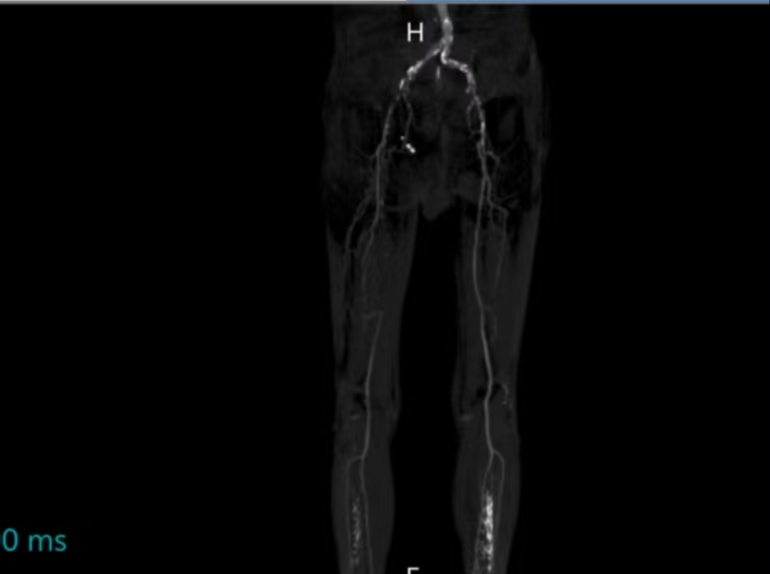

接诊医生是国壮心胸血管外科主任方恒晓。他详细查看了郭先生的下肢动脉CTA检查,发现他的双下肢动脉均存在严重狭窄及闭塞,且右下肢缺血更严重,血流受阻。如果不尽快处理,可能会因组织缺血坏死而面临截肢风险。

考虑郭先生为高龄患者,经过多学科讨论,医护团队决定采取微创腔内治疗方案,尽可能减少创伤、加快术后恢复速度。其中,“右髂动脉支架置入术”用支架撑开狭窄的动脉,恢复血流通畅;“右下肢动脉球囊扩张成形术”通过球囊扩张,进一步改善血管通路。

手术难度远超预期。郭先生的血管严重钙化,通路狭窄,导丝推进异常困难。方恒晓团队与介入科团队密切配合,身穿20多斤的铅衣,全神贯注坚守手术台6小时,经过反复调整、层层突破,最终成功打通闭塞血管,恢复正常血流。术后造影显示,血流恢复良好。